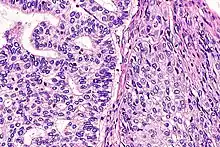

Micrograph of a lung primary small cell carcinoma, a type of carcinoma. The clustered cancerous cells consist primarily of nucleus (purple); they have only a scant rim of cytoplasm. The surrounding pale staining, discoid cells are red blood cells. Cytopathology specimen. Field stain. | |

- Small cell carcinoma

- Cells are usually round and are less than approximately 3 times the diameter of a resting lymphocyte and with little evident cytoplasm. Occasionally, small cell malignancies may themselves have significant components of slightly polygonal and/or spindle-shaped cells.[8]